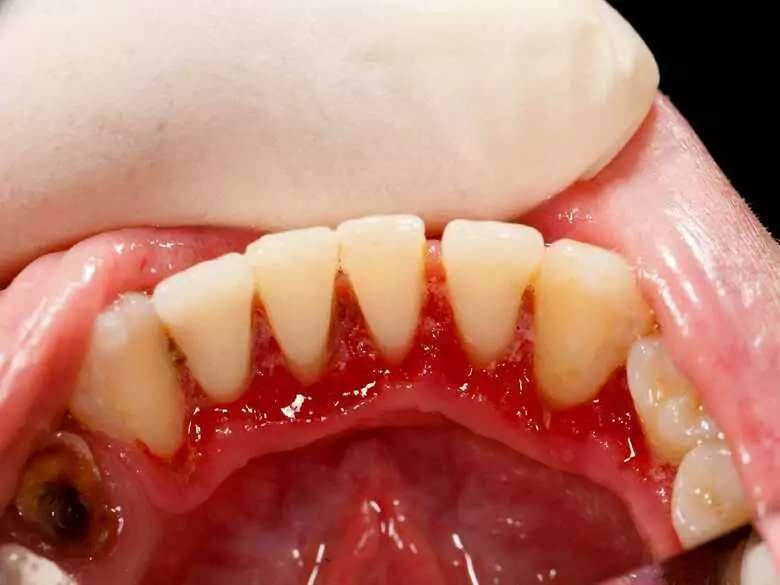

Objawy białaczki bywają różnorodne i zaliczane do nich bywają m.in. spadek apetytu, męczliwość i osłabienie odporności, ale i krwawienia z dziąseł. Ostatni z wymienionych problemów zazwyczaj dość zadziwia pacjentów – dlaczego osoby z białaczką miewają krwawiące dziąsła i jakie jeszcze zmiany w jamie ustnej mogą się pojawiać w przebiegu tej choroby?